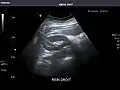

- Right kidney

Kidneys: Right and left kidneys measure 11.5 cm and 12 cm in length respectively. No hydronephrosis. Small left lower pole kidney cyst.